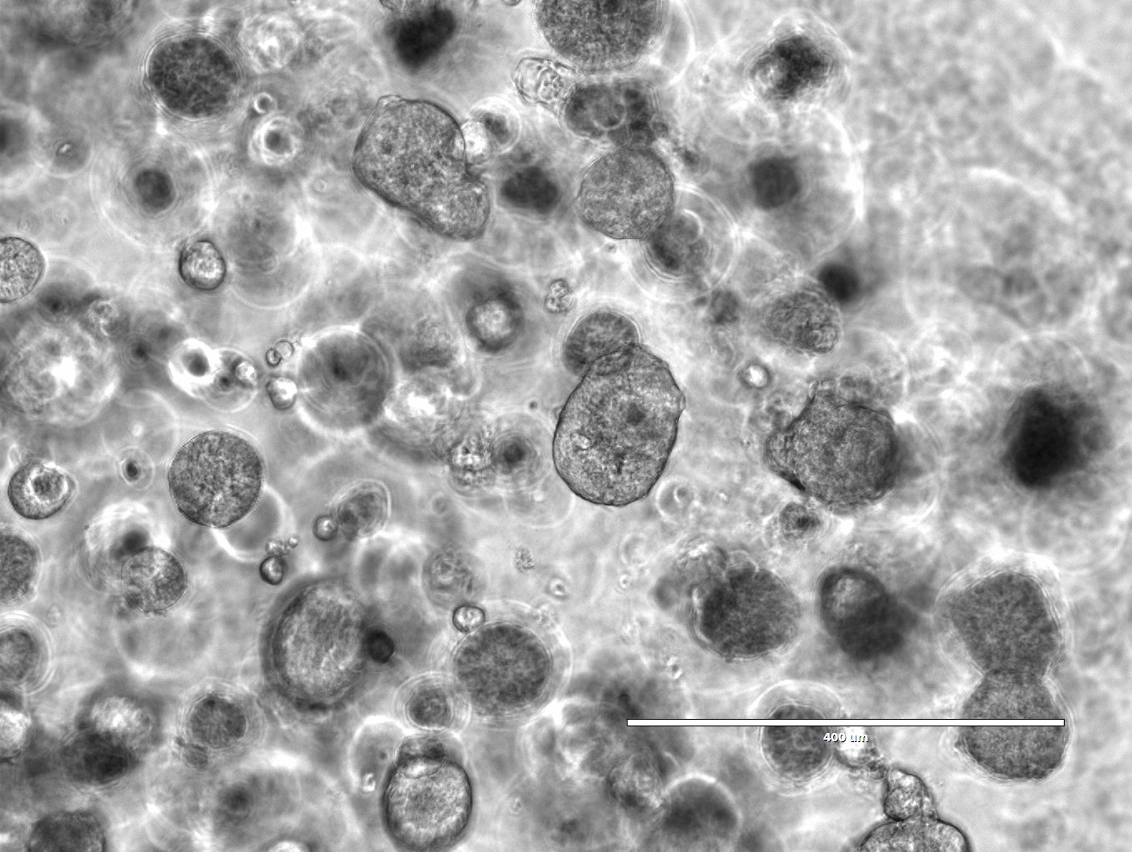

• 來源於乳腺癌病人的三維類器官形態觀察